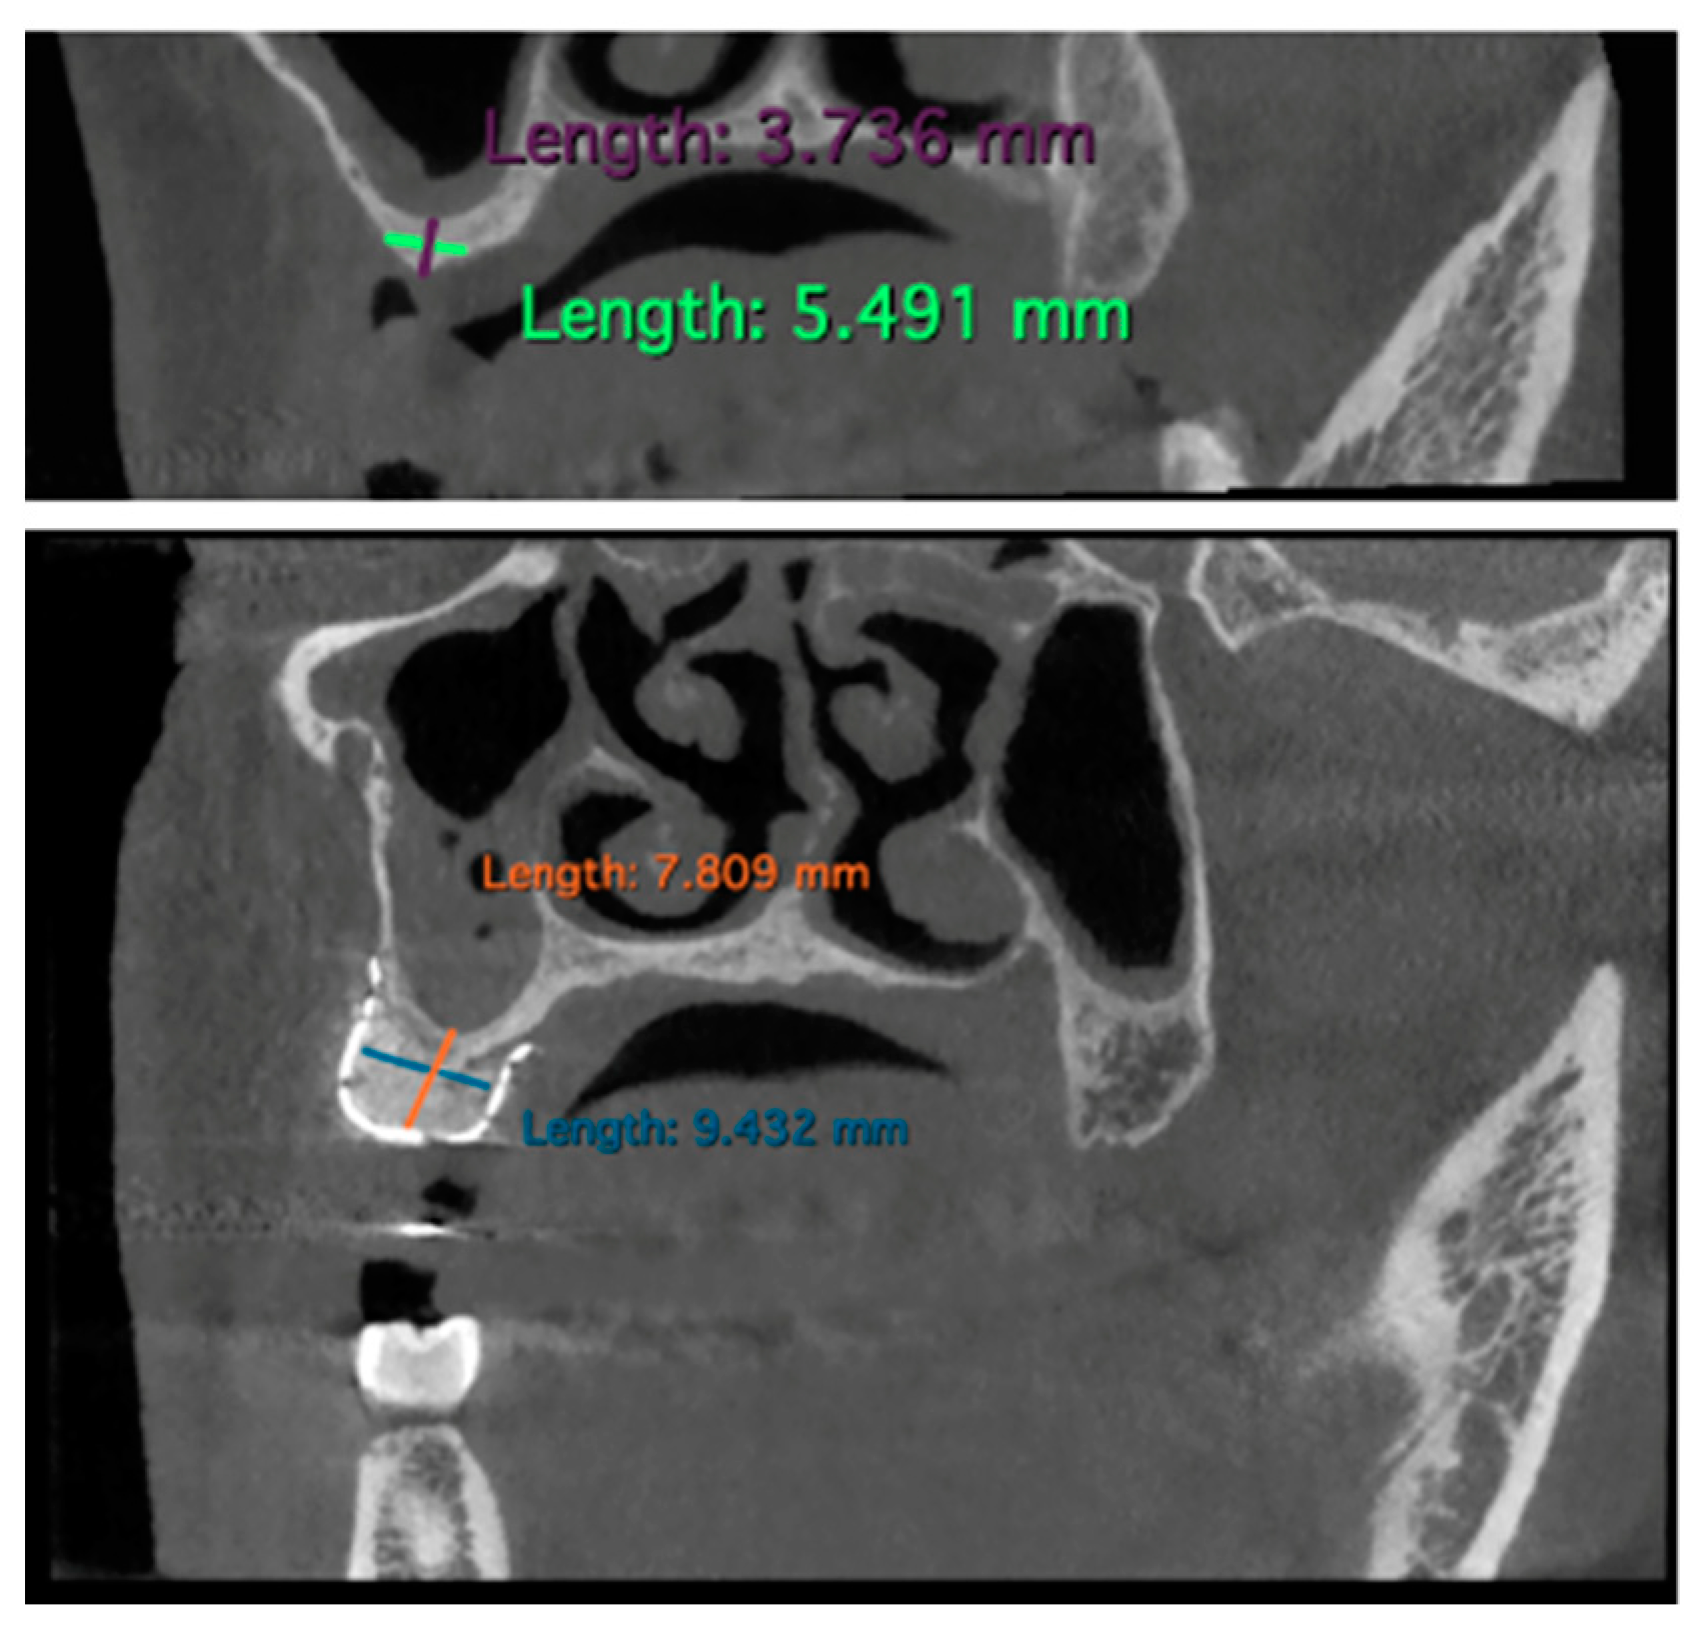

Bone gain measurements were conducted by comparing each patient’s preoperative and 6-month post-operative CBCT data.

Specifically, parasagittal images of the respective CBCTs were used as a reference for measuring bone defects. Mandibular bone defects were measured from the lower margin of the inferior alveolar nerve to the coronal portion of the bone defect. This approach aimed to prevent titanium mesh radiopacity from influencing post-operative result measurements, ensuring a complete identification of the inferior alveolar nerve.

The measurements were performed by using the software Horos Viewer™ (v.4.0.1) as shown in Figure 3.

Figure 3. Example of measurements performed on CBCT using the Horos Viewer™ software: pre-intervention and 6 months post-GBR (case n.10).